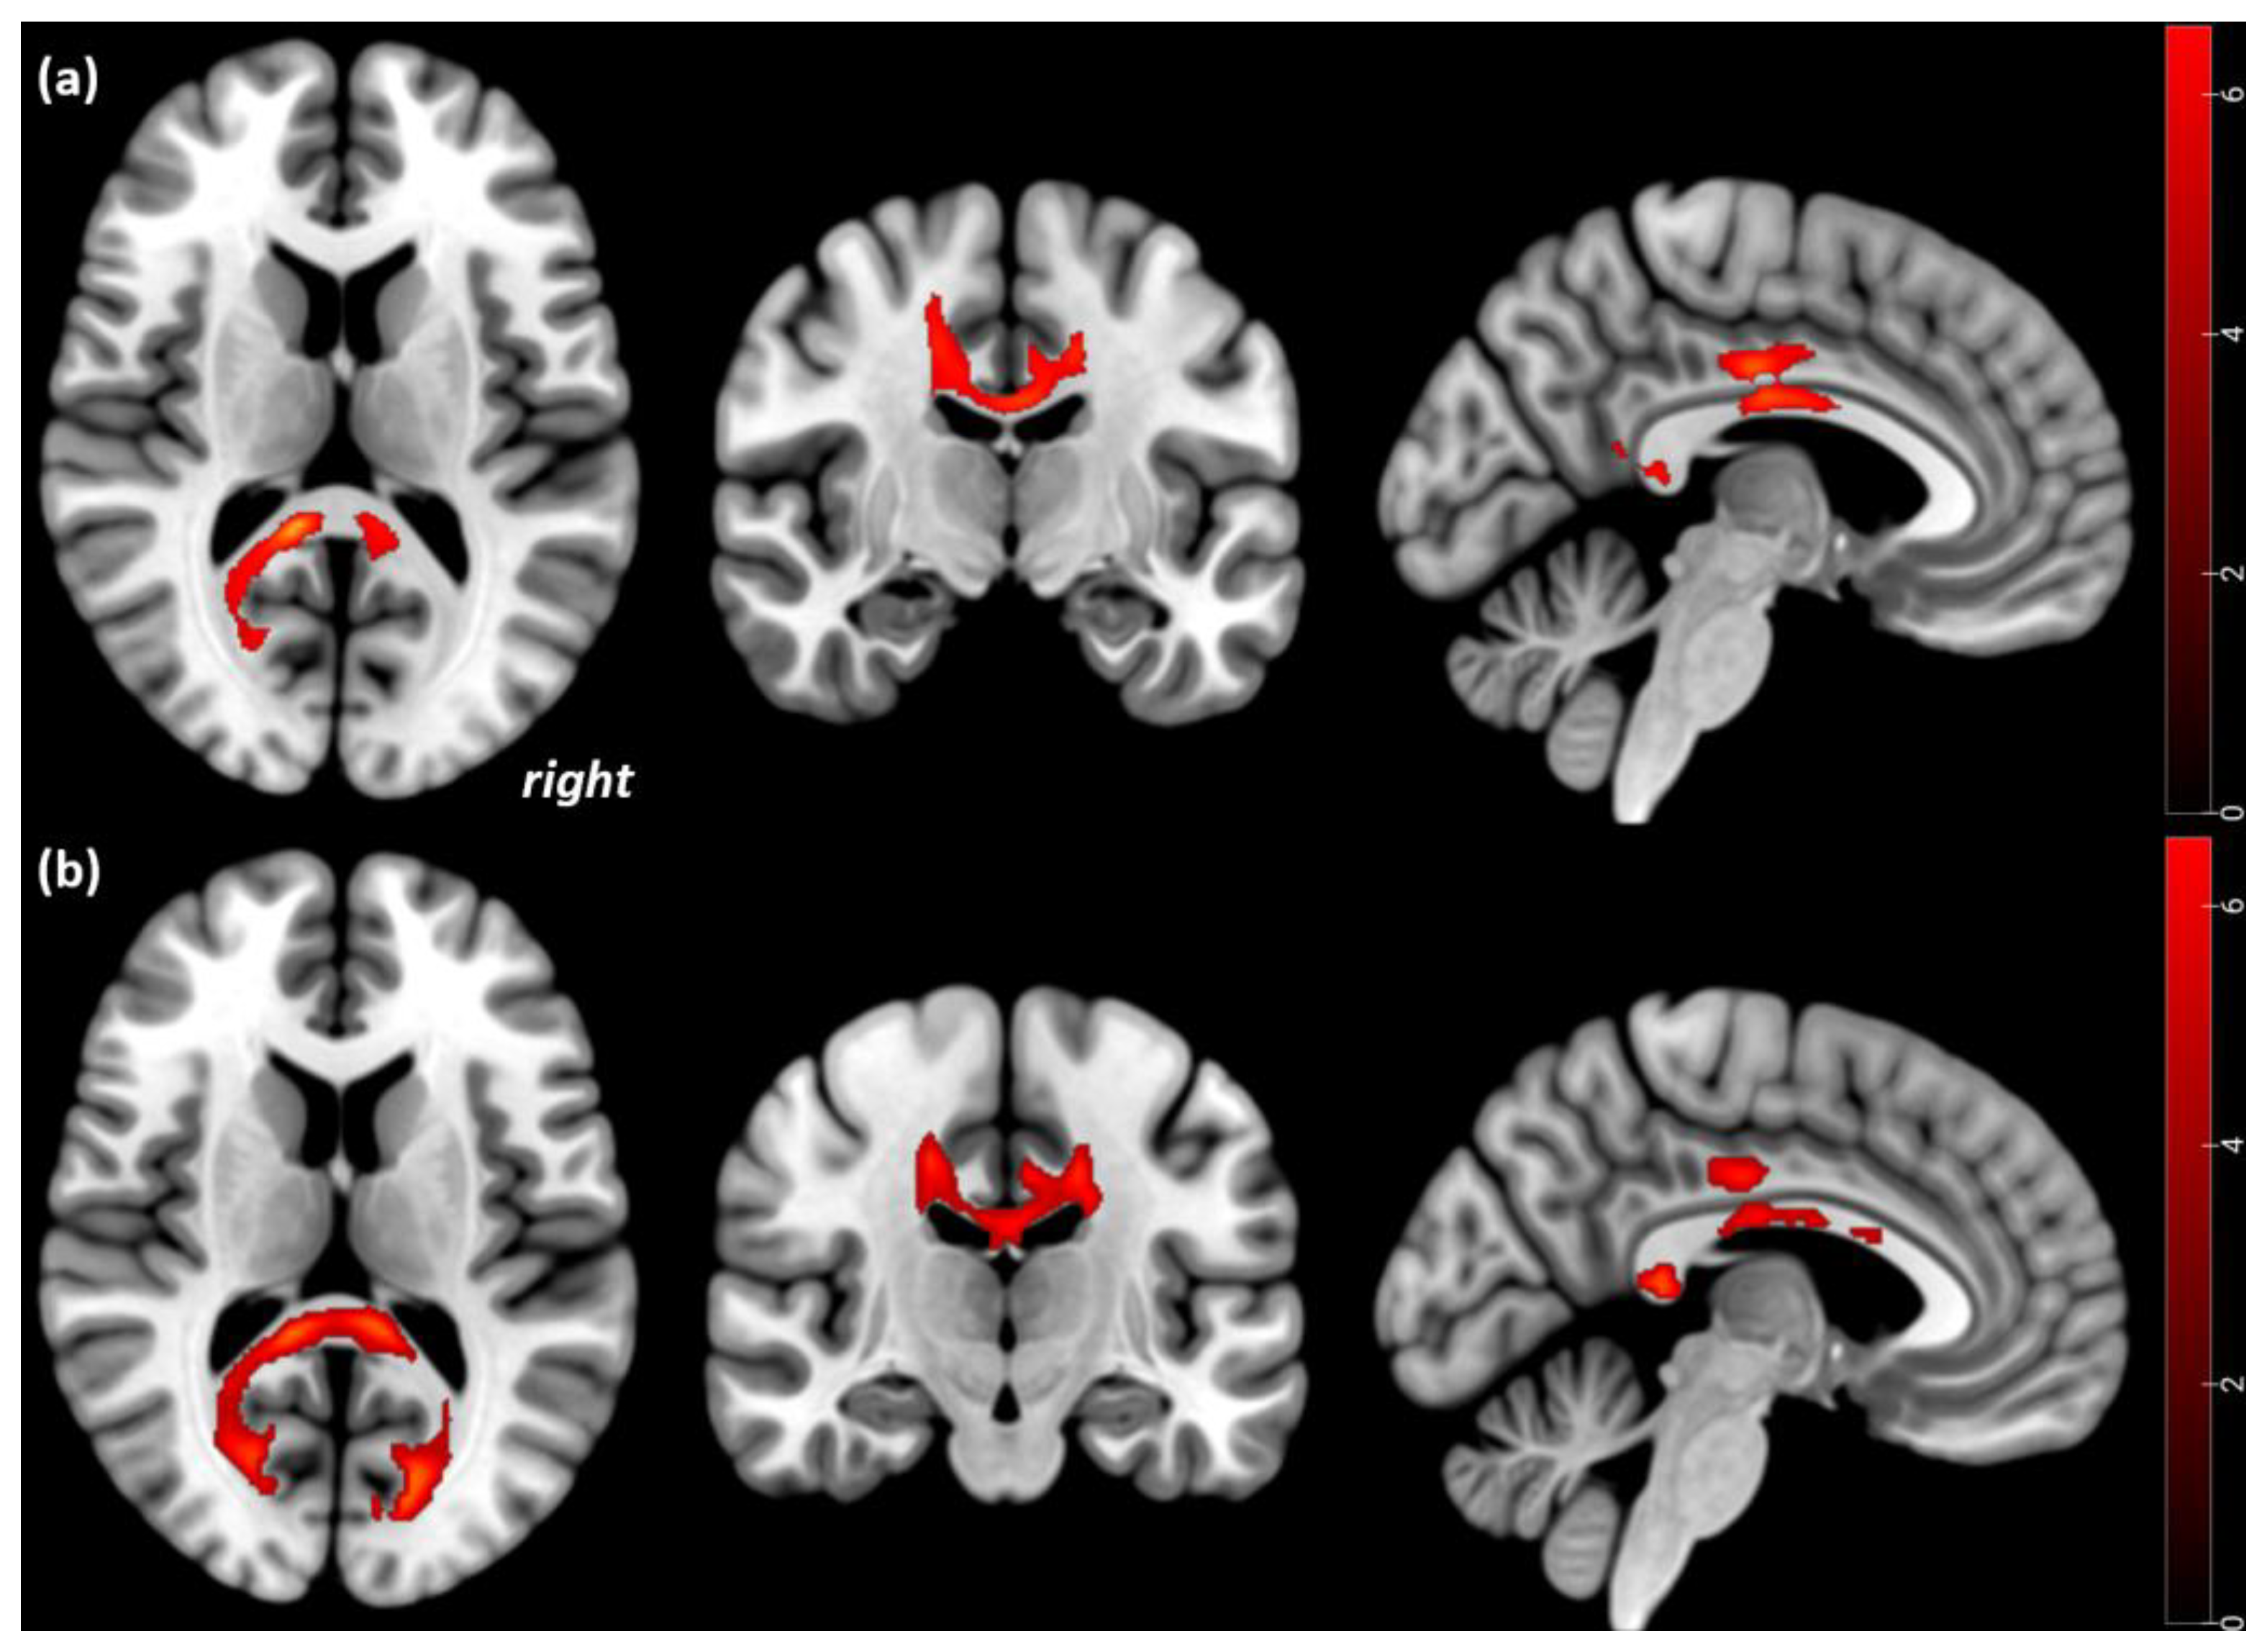

3.2. Cross-Sectional Comparisons of FA

3.3. Longitudinal Comparisons of FA

| Significant regional differences in FA values in the 21 AN patients compared to the 18 HC participants | |||||||

| Overlap of cluster region | kE | MNI coordinates | t value | p-value corrected at the cluster level (FWE) | Height Threshold | ||

| x | y | z | |||||

| Significant FA decreases in the 21 acute AN patients compared to the 18 HC participants at Tp1 | |||||||

| Corpus callosum and cingulum bilaterally spreading to the fornix, and the corticospinal tract | 1485 | 18 −20 14 | −20 −36 0.34 | 26 4 9 | 6.4 | <0.001 | 0.001 |

| Inferior occipitofrontal and longitudinal fasciculus left | 156 | −32 | −42 | −4 | 5.6 | 0.029 | |

| Significant FA increases in the 17 AN patients from Tp1 to Tp2 | |||||||

| Corpus callosum and cingulum bilaterally spreading to the fornix | 885 | 2 −4 4 | −12 −26 2 | 14 22 −1 | 6.7 | <0.001 | 0.001 |

| Inferior occipitofrontal and longitudinal fasciculus left | 165 | −34 | −42 | −4 | 4.5 | 0.008 | |

| Significant FA decreases in the 17 AN patients from Tp1 to Tp2 | |||||||

| Corticospinal tract, right | 125 | 26 | −24 | 30 | 8.1 | <0.001 | 0.001 |